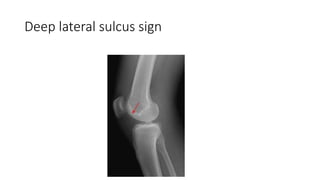

• Deep Lateral sulcus sign-Depression of lateral femoral condyle.

Deep lateral sulcus sign

Investigations • 1)X-ray ofthe knee-Anteroposterior and lateral view • See for seconds fracture-Avulsion fracture if lateral capsular ligament of knee which is ACL insertion site • • Deep Lateral sulcus sign-Depression of lateral femoral condyle.